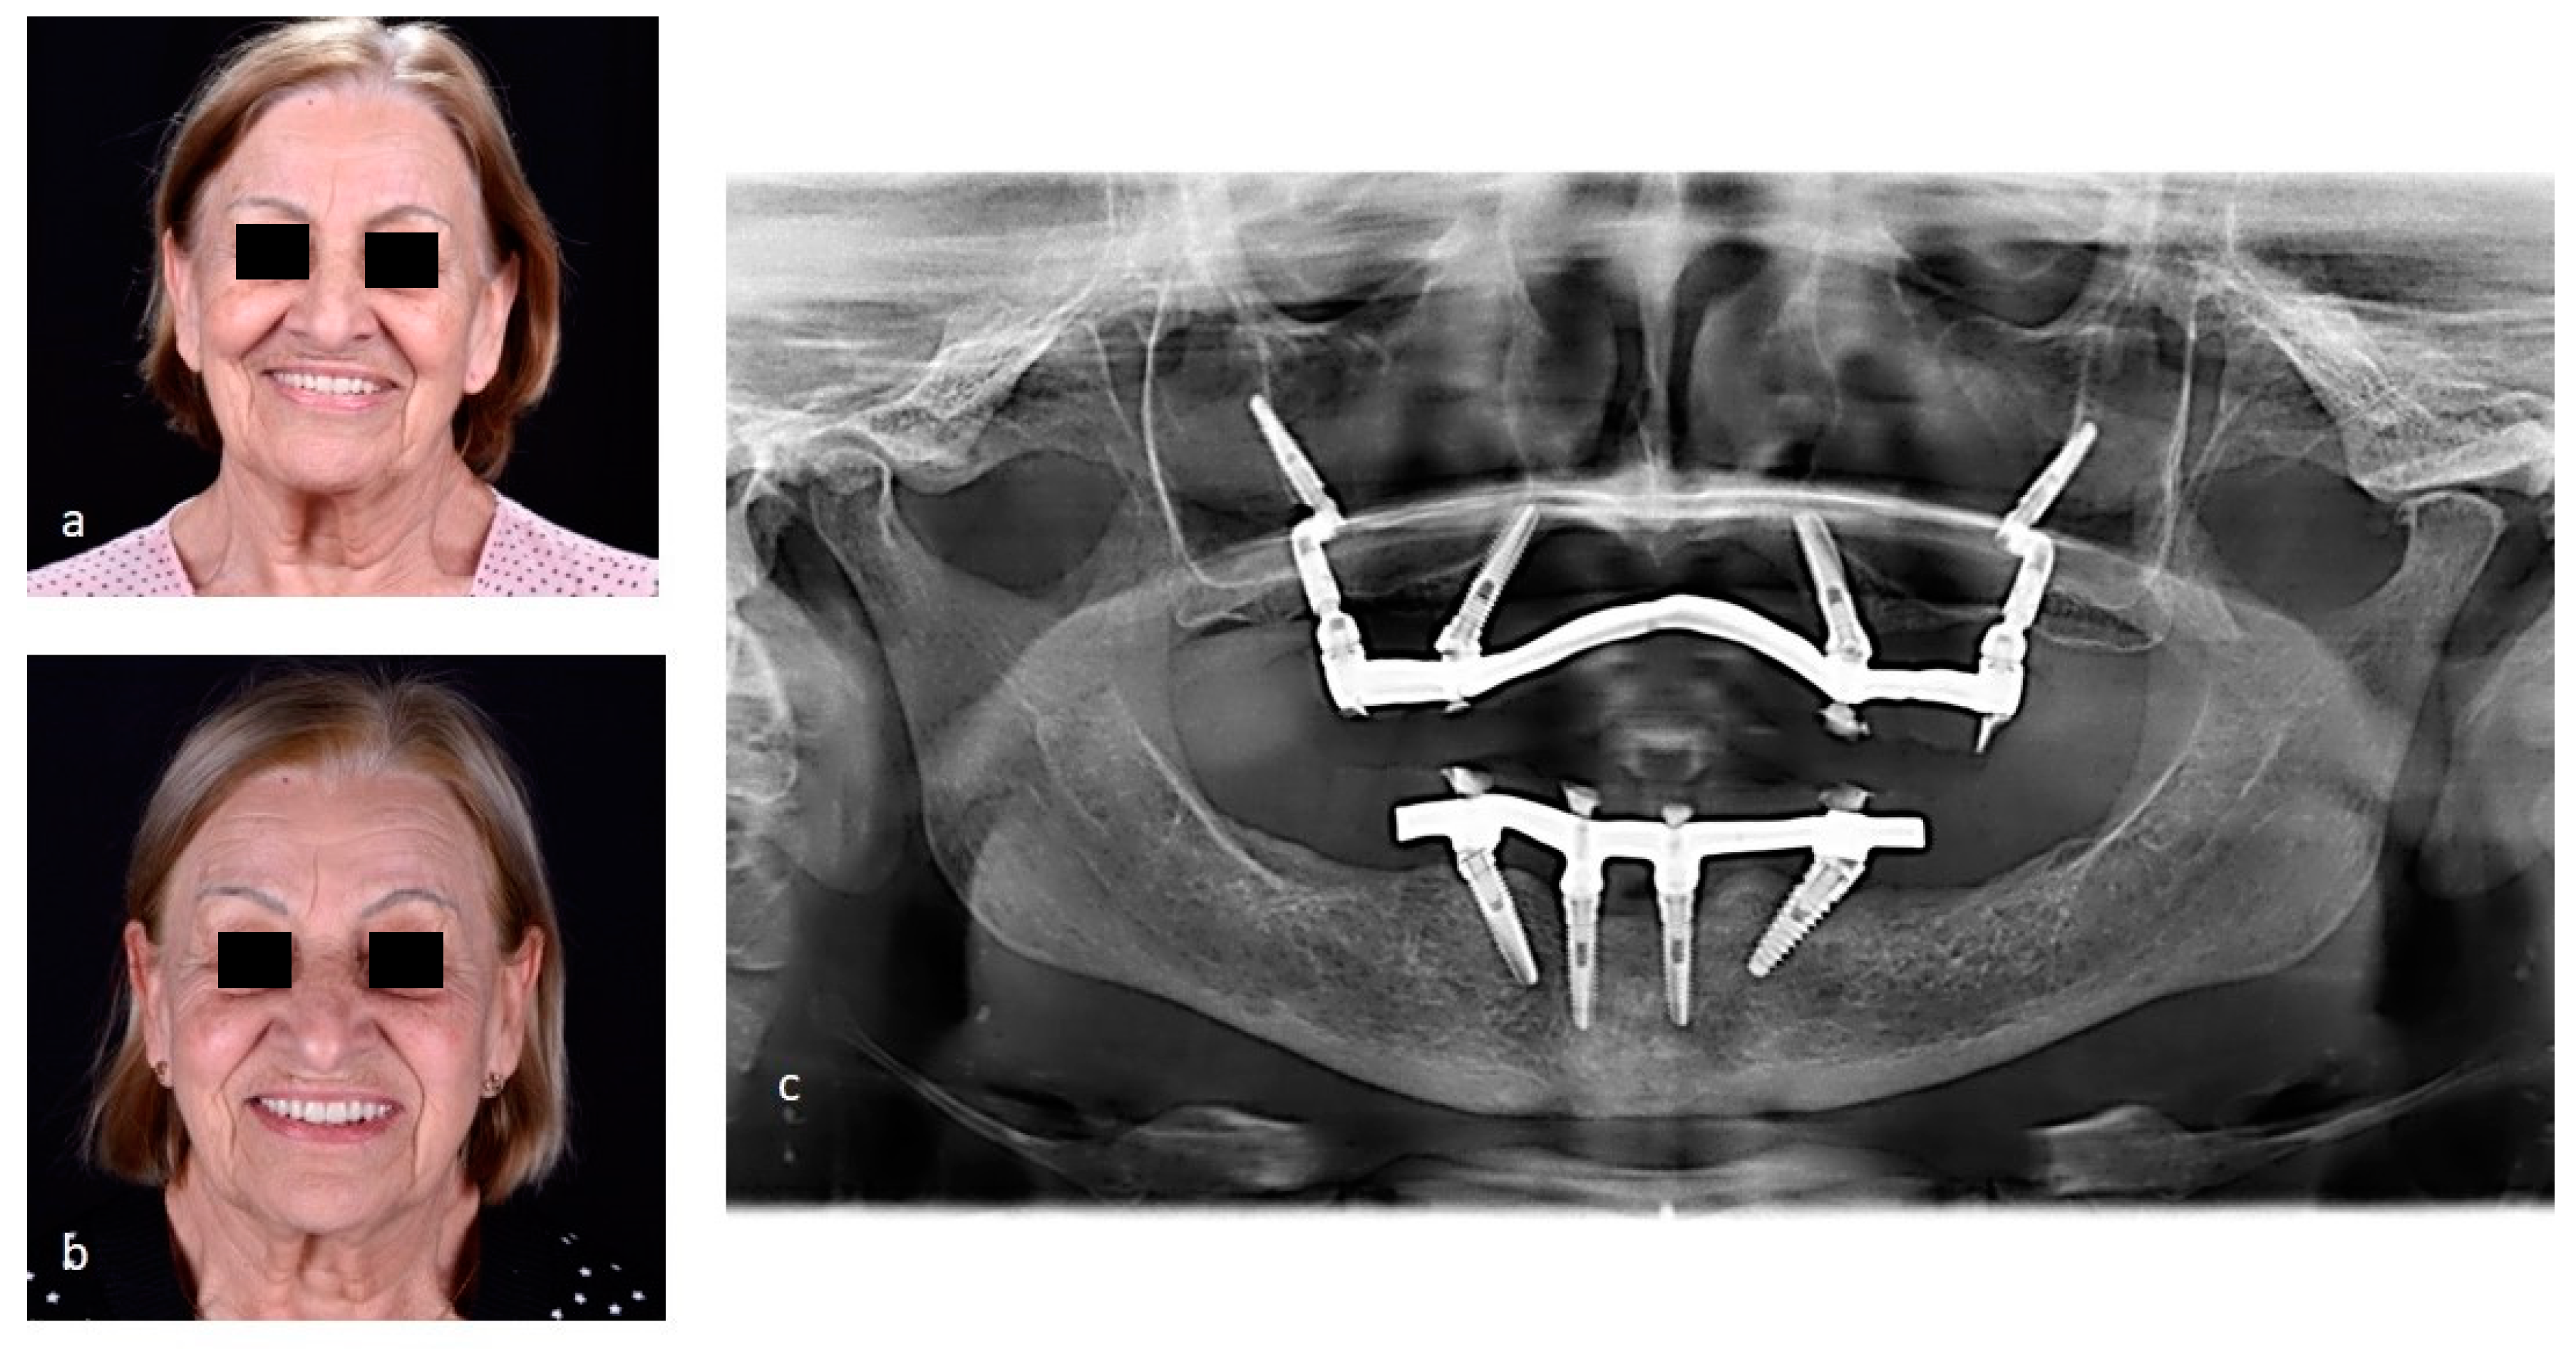

Figure 7.

The second case report shows the Facco technique used to rehabilitate a female patient, 58 years, without teeth or implants at atrophic maxilla and monitoring by 36 months after the surgical. A. Infiltrative anestesia at zygomatic arch. B. Incisions nealy zygomatic arch. C. Displacement gingival flap and suture to facilitate access at zygomatic area. D-G. Surgical sequence at right side until the setup pilar Z. H. Initial evaluation of the zygomatic boné. I. Milling cavity at zygomatic arch. J-M. Surgical sequence at left side. N. Implants positions favoring the posterior prosthetic rehabilitation. P. Initial panoramic radiography showing atrophic maxilary. Q. Final photo. R. Panoramic radiography final showing all-on-4 by Facco techinique.